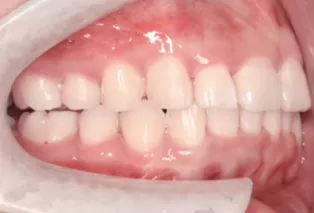

Photos intra-orales